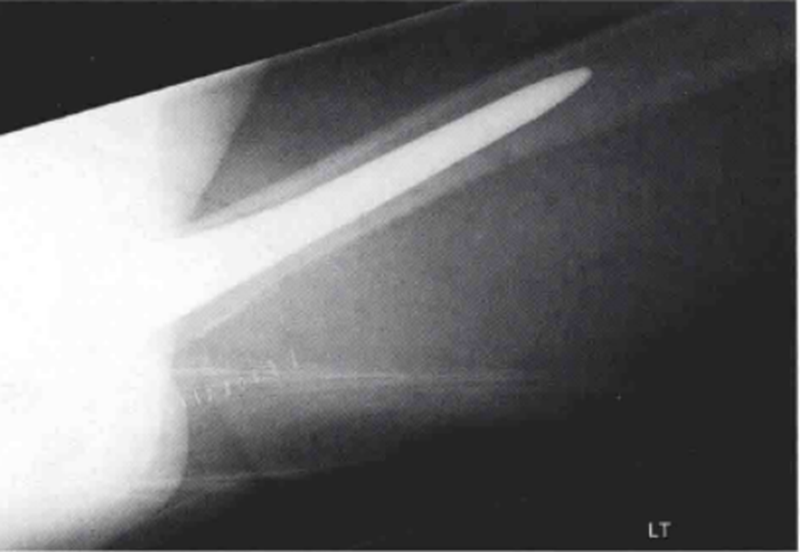

术后常规X线检查显示股骨近端可疑无移位骨折(图1和图2)。CT扫描证实了骨折的存在,且已对假体柄的稳定性造成了影响(图3)。

图2 初次全髋关节置换术后左髋侧位X线片,显示股骨近端一处可疑无移位骨折